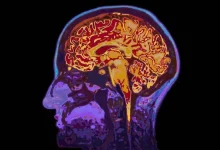

داشتن پسر میتواند باعث پیری سریعتر مغز والدین شود!

تحقیقات جدید دانشمندان نشان میدهد که داشتن پسر ممکن است باعث تسریع روند پیری مغز در والدین شود.

این یافتهها که حاصل مطالعهای گسترده روی بیش از ۱۳ هزار فرد بالای ۵۰ سال در ایالات متحده است، نشان میدهد والدینی که حداقل یک پسر دارند، در مقایسه با والدین بدون پسر، با سرعت بیشتری دچار کاهش تواناییهای شناختی میشوند.

به گزارش دیجیاتو، همچنین والدینی که بیش از یک پسر دارند، نسبت به والدینی که فقط دختر دارند، با سرعت بیشتری تواناییهای ذهنی خود را از دست میدهند.

تحقیق جدید که توسط تیمی از محققان دانشگاه چارلز در پراگ و دانشگاه کلمبیا در نیویورک انجام شده است، به بررسی علت این پدیده نپرداخته است، اما محققان پیشنهاد کردهاند که ممکن است این موضوع به دلیل حمایت عاطفی و مراقبت بیشتر دختران از والدین در سالهای سالمندی باشد. از سوی دیگر، والدینی که پسر دارند، ممکن است کمتر سبک زندگی سالمی را دنبال کنند.

به عنوان مثال، مطالعات نشان میدهد والدین دختر کمتر احتمال دارد که الکل مصرف کنند، مواد مخدر استفاده کنند یا سیگار بکشند، درحالیکه مادران پسران بهطور متوسط وزن بیشتری دارند.

در این مطالعه دادههای ۱۳ هزار و ۲۲۲ والد که به مدت حدود ۱۴ سال تحت نظر بودند، مورد بررسی قرار گرفتند. شرکتکنندگان تعداد فرزندان و جنسیت آنها را گزارش کردند و همچنین بهطور منظم تستهای شناختی انجام دادند که مهارتهای ذهنی مانند حافظه، تمرکز، تفکر و درک را ارزیابی میکرد.

نتایج این تحقیق که در مجله Journal of Psychiatric Research منتشر شده است، نشان میدهد والدینی که حداقل یک پسر دارند، در مقایسه با والدین بدون پسر، با سرعت بیشتری دچار کاهش تواناییهای شناختی میشوند. این کاهش تواناییهای ذهنی در هر دو والد، پدر و مادر، بهطور مشابهی وجود داشته است.

محققان خاطرنشان کردهاند که این اثرات در مقایسه با کاهش کلی تواناییهای شناختی در طول زمان «متوسط» است، اما حتی پس از در نظر گرفتن عوامل اجتماعی-جمعیتی و سلامتی که ممکن است نتایج را تحت تأثیر قرار دهند، همچنان قابل مشاهده بودند.

علاوهبراین، تحلیل دادهها نشان داده که کاهش تواناییهای ذهنی در والدینی که چندین پسر دارند، در مقایسه با والدینی که فقط دختر دارند، سریعتر است. از آنجا که این اثر در هر دو والد یکسان بود، محققان پیشنهاد کردند که جنبههایی از تربیت پسران ممکن است در پیری شناختی نقش داشته باشد.